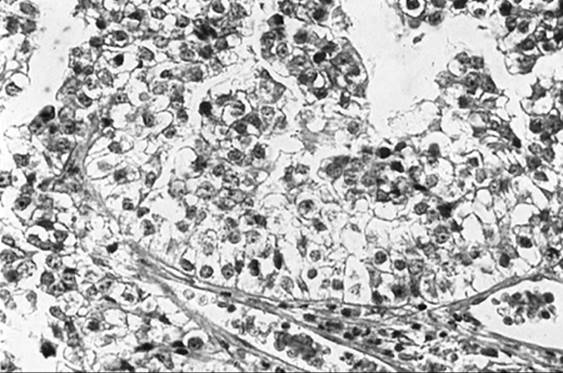

Paget disease accounts for 1% to 2% of vulvar malignancies. It occurs most frequently in postmenopausal white women and is characterized by red eczematous lesions with a superficial white coating and intense pruritis. As with other vulvar malignancies, there may be a long delay between initial symptoms and diagnosis. Histologic disease may spread well beyond the visible lesion. Biopsy reveals characteristic large eosinophilic cells in the basal layer of the epithelium (Fig. 51.12). Paget disease of the vulva may exist as four clinical entities, the first of which is noninvasive or intraepithelial Paget disease. This represents 60% of cases and is cured with local excision. In invasive Paget disease, the Paget cells penetrate the basement membrane and invade the dermis. Intraepithelial Paget disease may also be associated with an underlying adenocarcinoma of sweat gland origin or a coexistent cancer. Underlying malignancy is seen in approximately 20% to 30% of patients, a rate lower than that seen with mammary Paget disease. Parker and co-workers reported poor survival in patients with invasive Paget disease and in patients with underlying malignancy. Patients with clitoral disease also had a poorer prognosis. Therapy for Paget disease involves wide excision. A skinning vulvectomy with split thickness skin graft is often needed to remove large areas of involved skin. Recurrences tend to be local and range from 7% to 58% with an average of about 30%. Some authors recommend sending margins for frozen section to ensure complete resection while others have not demonstrated a benefit to this approach with respect to recurrence. Radical surgery is reserved for patients with underlying malignancy.

FIG. 51.12. Paget disease of the vulva. Large eosinophilic cells with large nuclei and prominent cytoplasm in basal cells represent Paget cells.